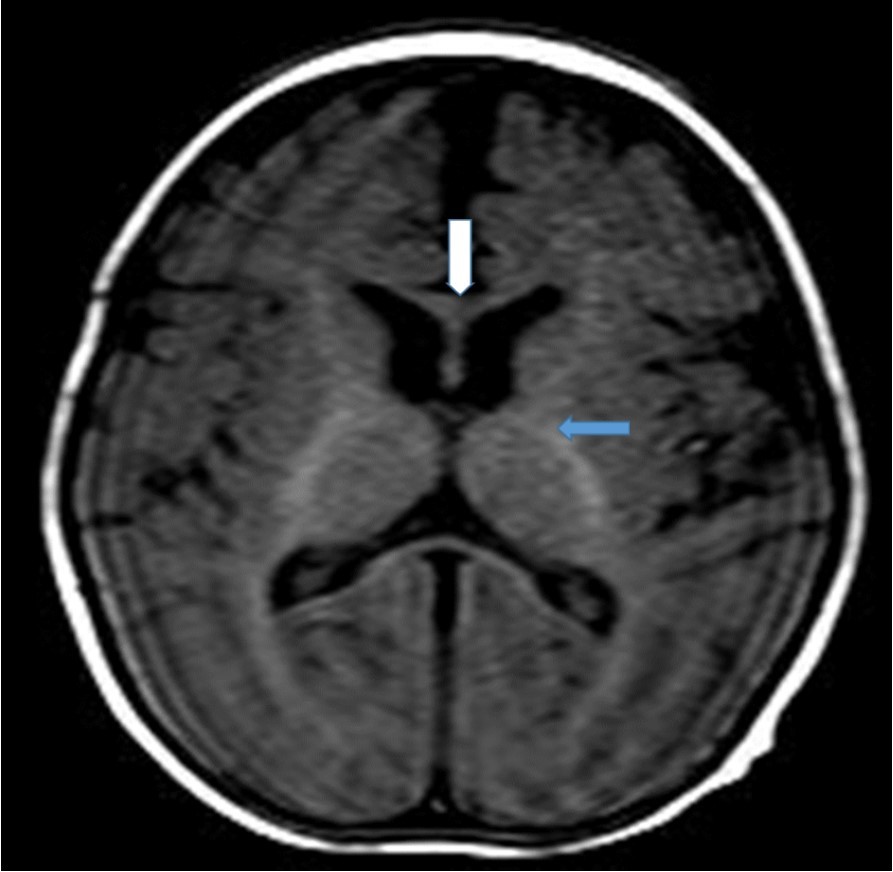

Cranial magnetic resonance imaging (MRI) was requested owing to the patient’s convulsion history and retarded development. The cranial MRI showed diffuse hypoplasia of the corpus callosum in the midline sagittal T2-weighted image (Figure 1 white arrow). T1-weighted imaging showed hypointensity due to delayed myelination of the genu of the corpus callosum (Figure 2, white arrow), which should normally appear hyperintense like the posterior limb of the internal capsule (Figure 2, blue arrow).

Figure 1.Midline sagittal T2-weighted magnetic resonance image of the patient showing diffuse hypoplasia of the corpus callosum.

Midline sagittal T2-weighted magnetic resonance image of the patient showing diffuse hypoplasia of the corpus callosum.